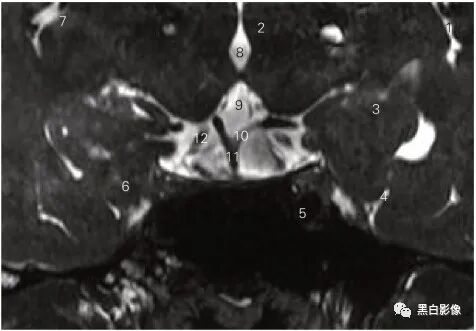

图5-4 经大脑后动脉的3D-SPACE序列冠状断层MR图像

1 外侧沟 lateral sulcus 2 背侧丘脑 dorsal thalamus

3 海马 hippocampus 4 侧副沟 collateral sulcus

5 颈内动脉 internal carotid artery

6 枕颞内侧回 medial occipitotemporal gyrus

7 岛叶 insular lobe 8 第三脑室 third ventricle

9 脑桥 pons

10 大脑后动脉 posterior cerebral artery 11 基底动脉 basilar artery

12 动眼神经 oculomotor nerve